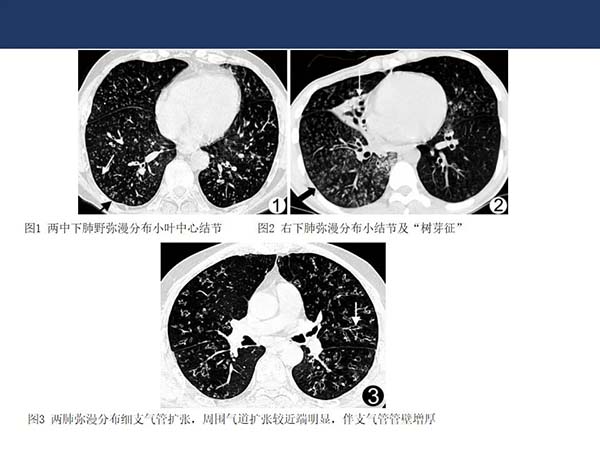

【杨柳病例】非结核分支杆菌肺病(NTMPD)